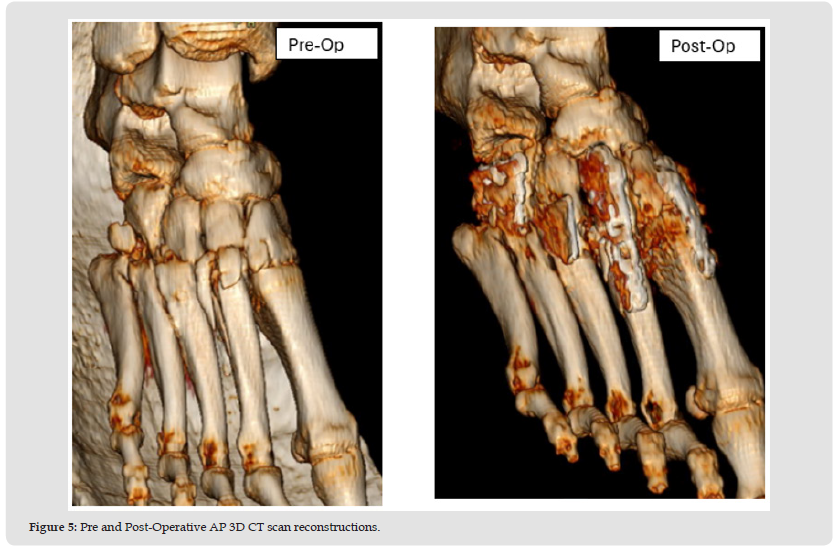

After a brief period in PACU the patient was discharged from the hospital and returned home. The patient was followed closely post-operatively. Pain, swelling, and ROM continuously improved at each visit while the patient was NWB. At the two-month follow-up some early consolidation of the bone graft was observed at the TMTJ grafted sites as evidenced on X-ray, with no pain following ROM of the mid-tarsal joint. At this point, the patient was instructed to begin partial weight bearing with her boot and a walker. Narcotic pain medication was no longer needed by the patient and discontinued by 10 weeks. At 12 weeks a CT scan showed bony bridging at the arthrodesis sites along with appropriate reduction of the Lisfranc complex. At 14 weeks the patient had transitioned to weight bearing in a regular shoe and reports no pain on physical examination. From this point the patient will return for follow-up only if needed.

Early bone graft consolidation was noted in this patient as early as 8 weeks post-operatively and was complete as evidenced on CT scan by 12 weeks. The early graft consolidation in this case is both interesting and encouraging. This case sets the stage for further research with long term follow-up using Catalyst Bone Graft for any foot and ankle procedure where bone graft is required for predictable and rapid healing (Figures 1-5).